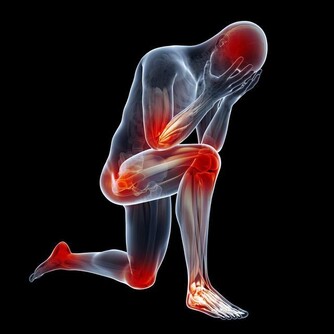

動脈堵塞血管硬化

高血脂幾乎沒有任何症狀,很多人血脂高也不知道,或者即便知道也不治療。往往很多人會突發心梗死、腦梗死等疾病,所以高血脂可以說是“無聲的殺手”。如果血脂升高,人體的動脈就會堵塞、硬化。

①心臟冠狀動脈堵塞,人體容易出現心肌梗死、心律失常、猝死等現象。

②腦動脈血管堵塞,或發生動脈硬化,可能出現腦血栓、腦梗死等現象,患者會癱瘓、昏迷、死亡等。

③腎動脈血管堵塞,或發生動脈硬化,可能導致腎功能衰竭、尿毒症等現象,患者往往需要進行洗腎、透析等,嚴重時還可能要換腎。

④四肢血管堵塞,或發生動脈硬化,可能很容易出現下肢動脈硬化閉塞症,下肢會發黑、疼痛,還會出現跛腳的症狀。